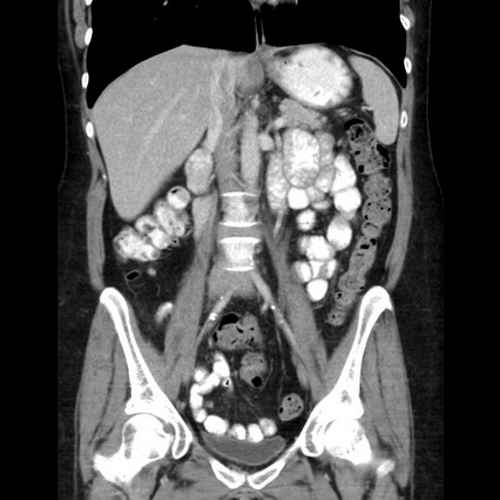

We have a huge number of cases with different modalities and regions

By Modality